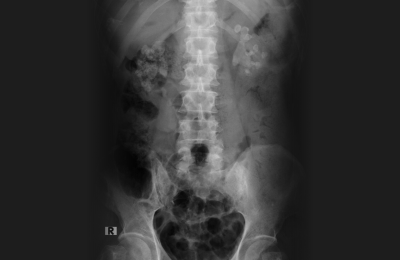

체외충격파 쇄석술은 고에너지 음파를 결석에 집중시켜 결석을 미세한 조각으로 분쇄하는 방식입니다.

초음파 또는 X-ray를 통해 결석 위치를 정확히 확인합니다. 충격파가 결석에 집중되도록 위치를 정밀하게 맞춥니다.